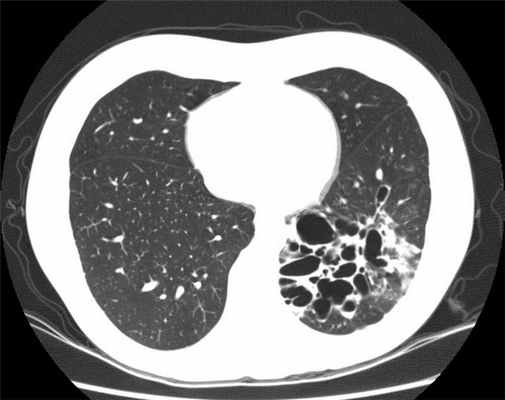

- КТ (компьютерная томография): это исследование необходимо для диагностики бронхоэктазов. При этом ваше тело подвергается рентгеновскому облучению под разными углами с последующим компьютерным составлением изображения с высокой точностью.

- если результаты КТ показали, что поражены оба легких или несколько частей, а не маленький участок легкого;

В окончательной постановке диагноза важнейшее значение имеют лучевые методы диагностики. При рентгенографии выявляются тяжистость, ячеистость, кистовидные изменения лёгочного рисунка, уменьшение объёмов отдельных зон лёгкого, эмфизематозность (воздушность) в смежных участках лёгкого. В настоящее время основным диагностическим исследованием является компьютерная томография (КТ, МСКТ). Это связано с большой информативностью метода при неинвазивном и безопасном характере его применения.